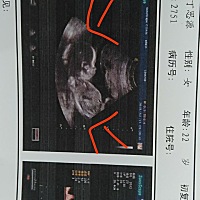

这是怀还是没怀,请帮忙看一下